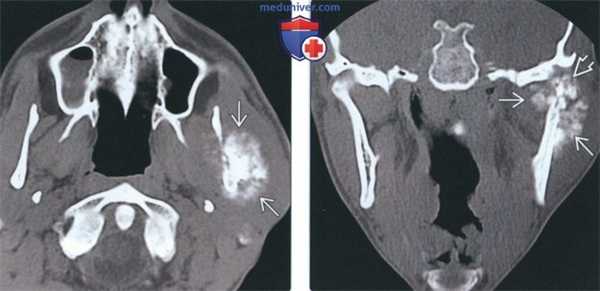

(Слева) На сагиттальной КЛКТ визуализируется крупная остеохондрома правого венечного отростка, имеющая луковицеобразную (или грибовидную) форму. Опухоль препятствует открыванию рта, упираясь в скуловой отросток верхней челюсти. Дифференциально-диагностический ряд включает гиперплазию венечного отростка, но при гиперплазии венечный отросток сохраняет свою форму.

(Справа) На корональной КЛКТ у этого же пациента определяется луковицеобразное увеличение венечного отростка за счет остеохондромы. (Слева) На аксиальной КЛКТ у этого же пациента визуализируется остеохондрома правого венечного отростка (сравните с неизмененным левым венечным отростком).

(Справа) На сагиттальной КЛКТ левого мыщелка на его передней поверхности визуализируется большая луковицеобразная остеохондрома. Внутренняя часть опухоли продолжается в неизмененную трабекулярную кость мыщелка. Определяется ремоделирование височной кости как приспособительная реакция к опухоли. (Слева) На трехмерной реконструкции (вид сбоку) у этого же пациента изнутри от скуловой дуги и выше нее визуализируется большая остеохондрома мыщелка.

(Справа) На корональной реформатированной КЛКТ у этого же пациента визуализируется большая луковицеобразная осге-охондрома мыщелка. Внутренняя часть опухоли образована трабекулярной костью с более выраженным участком склероза в центре. Обратите внимание на тонкий кортикальный слой на суставной поверхности.